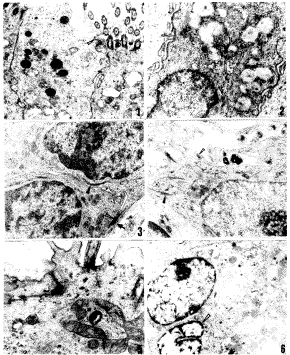

图1 右侧为纤毛柱状细胞,其表面有许多纤毛;左侧为无纤毛柱状细胞。两细胞近腔面见连接复合体(△)×8 000

图2 杯状细胞,核上方有较多粘原颗粒及粗面内质网。注意胞质内张力丝(△)×10 000

图3 纤柱上皮相邻的两个基底细胞,位于基膜(↑)上方,胞质内有成束的张力丝(▲),细胞间偶见桥粒连接(△)×12 000

图4 鳞状上皮之中层细胞,胞质内富含张力丝(▲),细胞表面有许多棘突,棘突间见桥粒连接(△)×8 000

图5 复层柱状上皮之表层细胞,其表面可见一纤毛 ×20 000

图6 腺上皮,其胞质内有丰富的粗面内质网及酶原颗粒。另一相邻的小细胞为基底细胞(△)×5 000